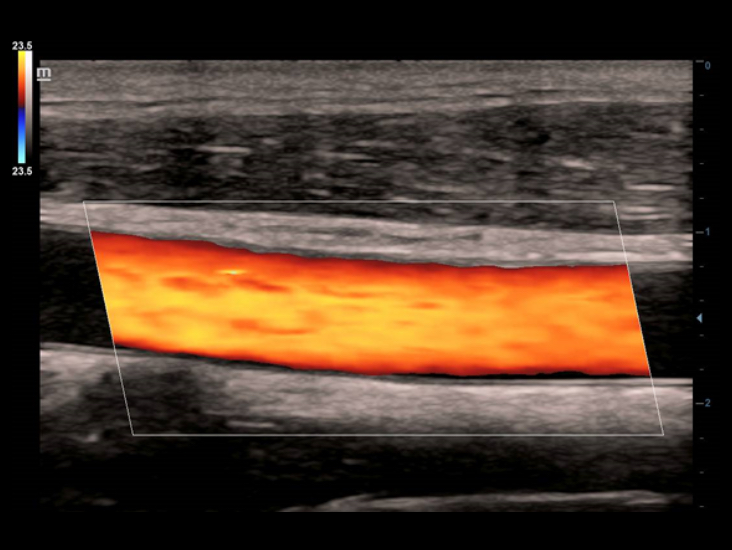

Full HD ??: ?? ??? ?? ??? ???.

'Full HD'? ?? ?? 1? ?? ???? ?? ???? ???? ??? ????? ?? ???? ??????. ??? ????? ??? ???? ???? ?? ??? ???, ??? ???, ??? ? ?? ???? ??? ??? ???.

'Full HD' ?????? ? ?? ???? Full HD? ?? DC-40? ???? ??? ??? ???? ??? ? ?? ?????. 'Full HD'? ??? ??? ????? ? ?? ?? ???, ? ?? ????? ??, ??? ? ?? ? ?? ??? ? ??? ??? ?????.